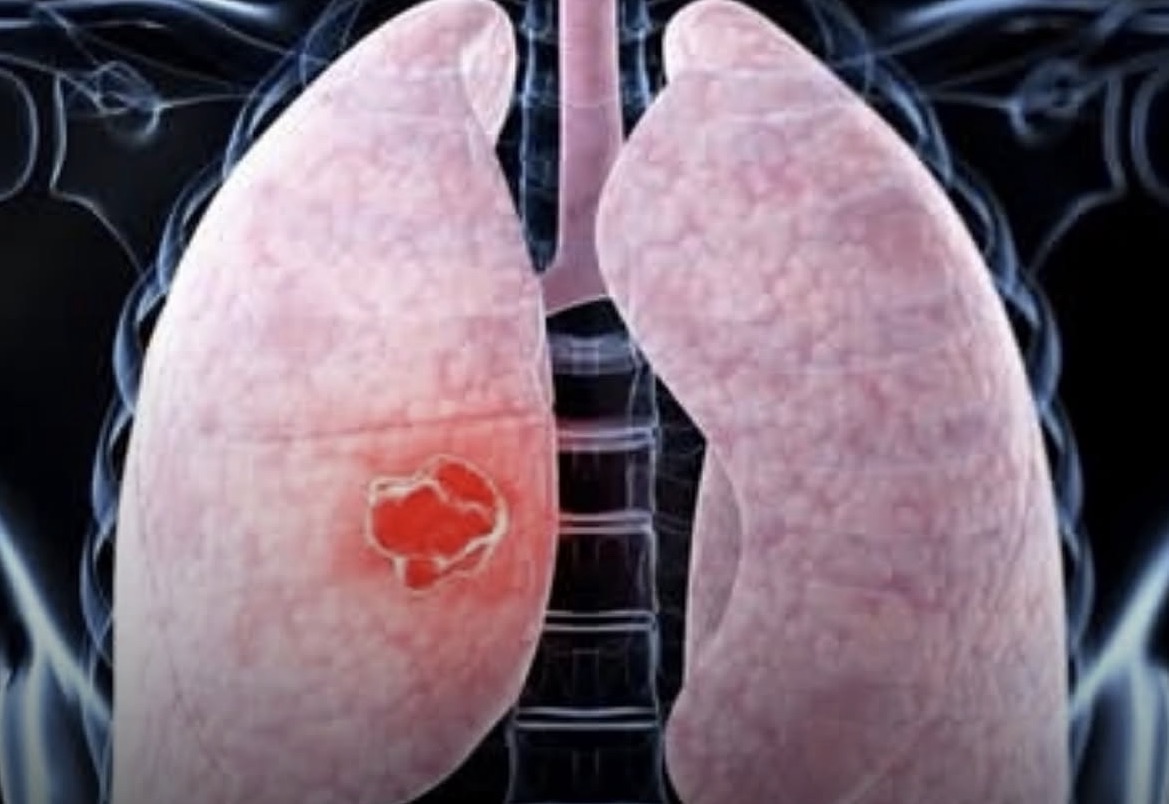

O câncer de pulmão continua sendo um grande desafio para a saúde pública. Na maioria das vezes, o diagnóstico ocorre tardiamente, o que dificulta o sucesso do tratamento. O tabagismo segue como principal fator de risco, mas especialistas alertam que outros elementos, como exposição à poluição e fatores genéticos, também podem influenciar no desenvolvimento da doença.